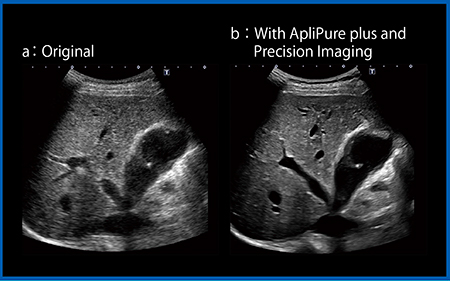

超音波画像にはスペックルと呼ばれるノイズが現れて読影の邪魔となる。例えば,病変が不明瞭なオリジナル画像(図5 a)にApliPure plusとPrecision Imagingを適用するとスペックルノイズが低減し,小囊胞による多重反射が多数認められ,びまん性の小囊胞であることがわかる(図5 b)。演者は,ApliPure plus 2とPrecision 2の条件設定を頻用している。

図5 ApliPure plusとPrecision Imagingによるスペックルノイズの低減